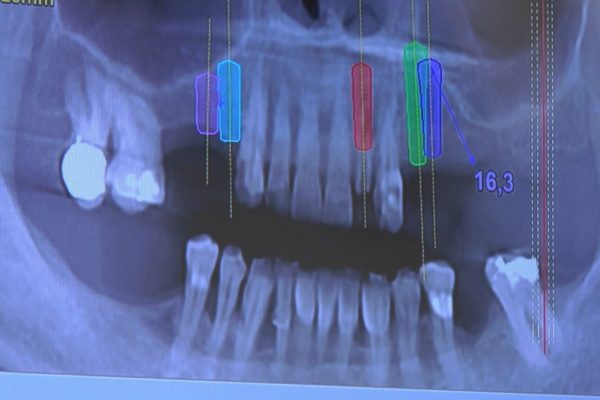

W ostatni weekend czerwca 2018 roku kursanci II Sezonu Preludium Implantologii odbyli piątą, finałową sesję, która w całości podporządkowana była praktyce. W ciągu dwóch dni zabiegowych Lekarze uczestniczący w szkoleniu przeprowadzili szereg zabiegów pod kierunkiem dr n.med. Violetty Szycik. Wszczepili 17 implantów oraz przeprowadzili ekstrakcje i zabiegi regeneracyjne kości. Zabiegi były wykonywane także w sedacji dożylnej z udziałem specjalisty anestezjologii i intensywnej terapii dr Jolanty Grzybowskiej. Preludium implantologii to nowy program edukacyjny dla adeptów implantologii stomatologicznej, którego celem jest wprowadzenie do implantologii poprzez pozyskanie wiedzy w szerokim zakresie i uwzględnieniem szczegółów mających decydujące znaczenie dla powodzenia leczenia implantologicznego. Ale tak jak wszystkie szkolenia w Instytucie Vivadental, w tym wiodące Practiculum Implantologii, zorientowane jest na praktyce i samodzielnym wykonywaniu zabiegów pod kierunkiem Mentora. To najlepsza edukacja w medycynie zabiegowej, a zarazem najlepszy start do implantologii.